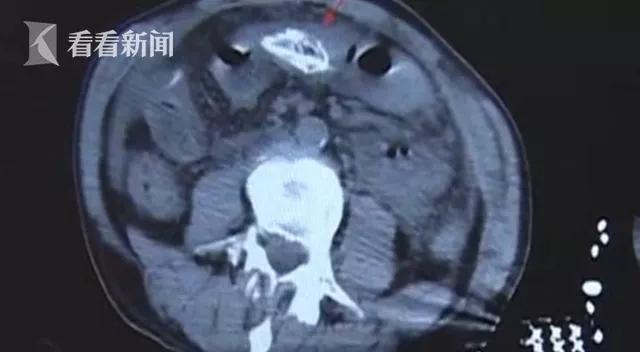

医生介绍道,该男子前来就诊时表情痛苦、心情烦躁,再加上其血压下降,表现为感染性休克。医生通过腹部CT检查初步判断他的腹腔有异物。

随着时间的推移,这名男子已经疼得无法与人正常交流了。医生根据他的症状、体征,结合腹部CT检查,判断为消化道穿孔。通过腹腔镜探查,医生这才看清,男子腹中的异物竟然是一条黄鳝!

主治医生表示, 黄鳝进入了患者的腹腔后已经死亡,致该患者的腹腔污染非常严重, 有大量淡绿色的渗液,腹壁、肠道、肝脏等多处附着大量的脓苔和粪便。 可以确定患者是黄鳝所导致的“乙状结肠破裂”。

最终,医生通过手术取出了男子腹中这条长约40厘米的黄鳝。经过院方及时医治,男子现已康复出院。